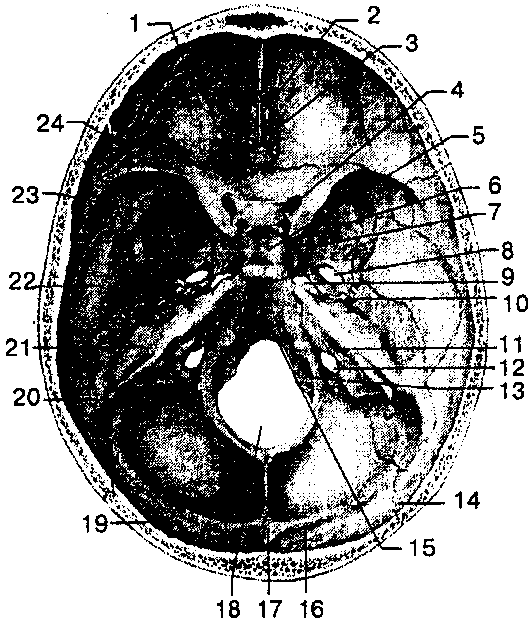

1 — глазничная часть лобной кости; 2 — петушиный гребень; 3 — решетчатая пластинка; 4— зрительный канал; 5 — гипофизар-ная ямка;. 6— спинка седла; 7 — круглое отверстие; 8 — овальное отверстие; 9 — рваное отверстие; 10— остистое отверстие; 11 — внутреннее слуховое отверстие; 12 — яремное отверстие; 13 — подъязычный канал; 14 — лямбдовидный шов; 75 — скат; 16 — борозда поперечного синуса; 77—внутренний затылочный выступ; 18 — большое (затылочное) отверстие; 19 — затылочная чешуя; 20 — борозда сигмовидного синуса; 21 — пирамида (каменистая часть) височной кости; 22 — чешуйчатая часть височной кости; 23 — большое крыло клиновидной кости; 24 — малое крыло клиновидной кости